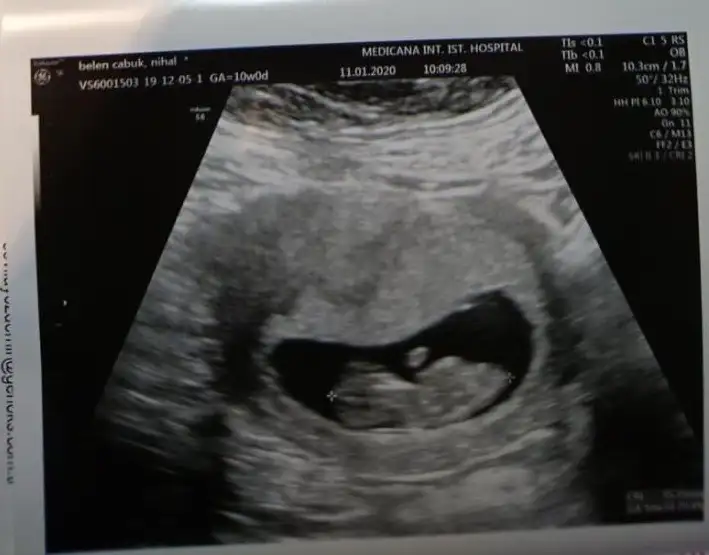

Net degil usg eminde değilim sanki kız varda başka usg paylaşın emin değilim

11 yada 12 hafta varmı

Kız bence 9+6 hafta ya göre

Buda kız gibi boş görünüyor bacak arasıdün gittik 14 hafta usg verdi ama belli olmuyor Eki Görüntüle 2575104